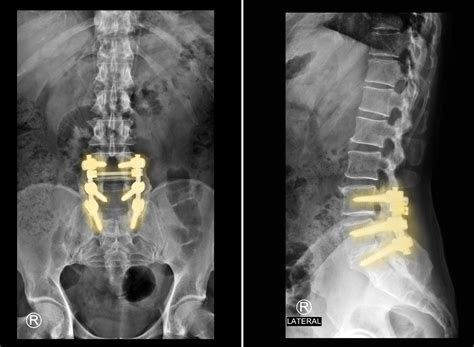

Bone Graft or Implant Insertion

A bone graft or implant is inserted into the disc space. The graft can be autologous (from the patient's own body), allograft (from a donor), or synthetic. The implant is designed to promote fusion and provide structural support.

The vertebrae are stabilized using screws, rods, or plates. The incision is then closed in layers, and the patient is taken to the recovery room.